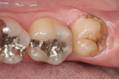

ここで説明するのは半埋伏歯の場合です。智歯の位置は口の一番奥にあり、鏡で見てもなかなか見えません。特に上顎は直視できません。左の写真にあるとおり一部は歯肉が被さっており、多くの場合歯肉のふところは通常のポケットよりも深くなっています。このふところ部分にプラークが溜まったままでいると歯肉に炎症が生じます。それを防ぐためには日常の的確なブラッシングが大切です。通常の歯ブラシを少し立てるようにして毛先を歯肉のへり(「辺縁」といいます)に当て小さく動かします。またはチップブラシの先端で辺縁をなぞるようにします。